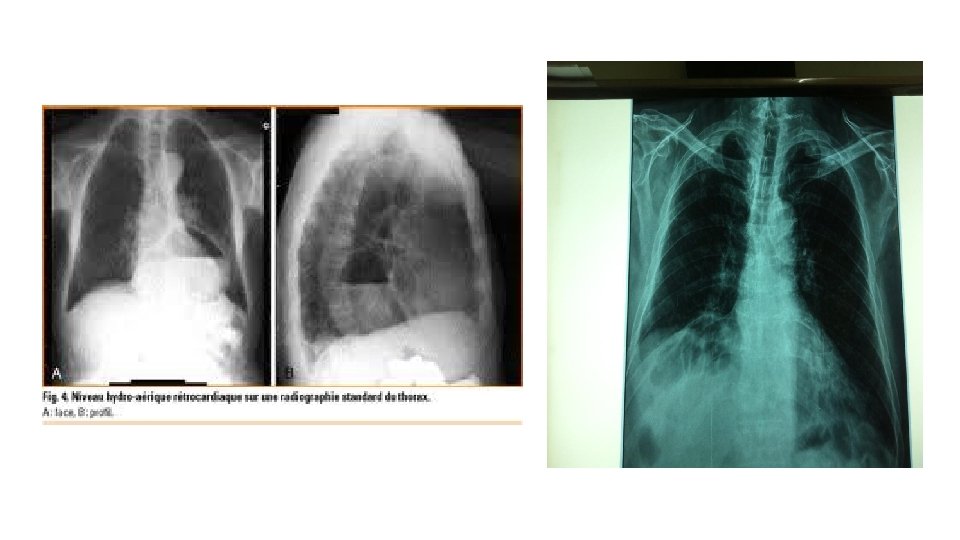

L’emphysème • L’hernie diaphragmatique L’hémi thorax gauche est le siège de clartés arrondies avec niveau hydro aérique occupant la base semblant en continuité avec des clartés digestives visibles à travers l’ombre cardiaque effaçant l’hémi coupole diaphragmatique